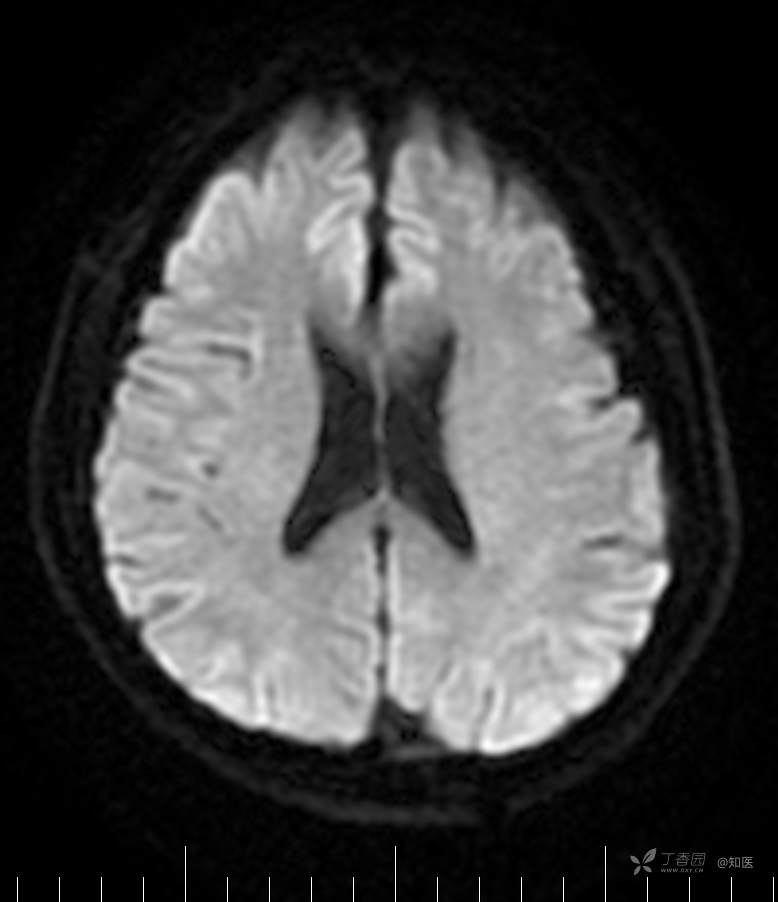

2021-6-15 ADC

2021-06-16日晨查房,患者自觉入院治疗后肢体无力症状较前稍改善,仍有活动后气短,余未诉特殊不适。ALSFRS-R评分:44分(单项均大于等于2分)。血压:123/63mmHg。神经系统查体:GCS 15分,右利手,查体合作,问答切题,粗测智能基本正常。额纹对称,双眼闭目紧,双侧瞳孔等大等圆,直径约3.0mm,对光反射灵敏,眼球运动自如,无眼震,双侧鼻唇沟对称等深,口角无歪斜。悬雍垂居中,双侧软腭抬举良好,咽反射灵敏、转颈、耸肩均一致有力。颈屈肌、颈伸肌力量5级。伸舌居中,无舌肌纤颤及萎缩。双侧岗上肌、岗下肌可见萎缩;双侧三角肌可见偶发肉跳、肌力5级,左侧肱二头肌肌力4+级、右侧4-级,双侧肱三头肌肌力4+级;双手握力可,双手大小鱼际肌及第一骨间肌可见萎缩,左侧明显,左侧手腕背伸力量4级、右侧4+级,双侧拇短展肌肌力4-级,双侧示指伸肌肌力3级,左侧指总伸肌肌力4级、右侧4-级,双侧小指展肌肌力4-级。双上肢肌张力对称减低。左侧肱二头肌反射迟钝、右侧未引出,双侧桡骨膜反射及肱三头肌反射未引出。左侧胸大肌反射阳性、右侧未引出,双侧Rossolimo征阳性、Hoffmann征阴性,下颌反射阴性。腹壁反射未引出。双下肢可见肌肉萎缩,以左侧明显;左侧髂腰肌肌力4级、右侧4-级,双侧股四头肌肌力5级,双足背伸力量3级,左足跖屈力量4级、右足4+级。双下肢肌张力对称基本正常。双侧膝腱反射、跟腱反射迟钝,双侧跖反射消失,双侧巴氏征未引出。右侧大腿外侧肌肉活检瘢痕周围浅感觉缺失,余肢体及躯干深浅感觉正常,共济运动对称正常。颈软,无抵抗,双侧布氏征及克氏征均阴性。辅助检查:微量元素(钙、镁、铁、铜、锌),微量元素测定(铅,镉)[复][2021-6-16 16:11:07]:钙1.19mmol/l;铁9.00mmol/L。急诊电解质七项[复][2021-6-16 10:41:41]:钾3.55mmol/L。血细胞分析+五分类[2021-6-16 9:57:17]:淋巴细胞百分比19.5%。[头颅,扩散成像(DWI)][头颅,磁敏感成像(SWI)][头颅,水抑制成像(FLAIR)][2021-6-16 18:10:50]:1.多发腔梗,脑白质脱髓鞘,脑萎缩。2.DWI:脑实质内未见明显高信号。3.磁敏感成像脑实质内未见明显异常信号灶。MMSE:26分(高中文化水平)。MoCA:23分。ADL评分:14分。ECAS评分:96分(ALS特异67分、ALS非特异29分)。肌电图:提示颈髓、腰髓、胸髓和延髓支配肌肉可见活动期神经源性损害,颈髓和腰髓支配肌肉同时可见慢性期神经源性损害;提示脊髓前角细胞损害可能,请结合临床。心电图大致正常。外送基因检查:TBK1基因杂合子,提示额颞叶痴呆和(或)肌萎缩性侧索硬化症4型。二线主治医师查看患者后示:1.患者基因检查结果显示TBK1基因杂合子,提示额颞叶痴呆和(或)肌萎缩侧索硬化症4型,结合外院影像学检查可见额颞叶萎缩明显,来院后复查头颅FLAIR+DWI+SWI亦提示脑萎缩,量表评估提示认知功能稍减退,ECAS评分基本正常。综上,修正诊断:肌萎缩侧索硬化症(ALS) 额颞叶变性 低钾血症 高血压2级(高危) 多发腔隙性脑梗死。因TBK1基因引起的额颞叶痴呆和(或)肌萎缩侧索硬化症为常染色体显性遗传,患者父亲已逝,母亲健在,诉无明显认知功能障碍或肌肉萎缩等表现,建议患者母亲抽血送检,进一步明确致病基因来源,必要时患者子女也可行基因检查进一步明确。2.患者目前诊断基本明确,根据文献报道,合并FTD的ALS患者整体生存周期较短(约19个月),目前患者发病已1年余,应充分与患者家属沟通病情,告知疾病预后及生存周期情况,同时建议开始口服利鲁唑片,延缓疾病进展。余治疗方案暂不予调整。密观病情变化,遵嘱执行。

2021-06-18出院总结: 卫某某,男,60岁,以“四肢僵硬1年,加重伴无力半年”之主诉入院。查体:生命体征平稳,心肺腹查体无明显异常。神经系统查体:GCS 15分,右利手,查体合作,问答切题,粗测智能基本正常。额纹对称,双眼闭目紧,双侧瞳孔等大等圆,直径约3.0mm,对光反射灵敏,眼球运动自如,无眼震,双侧鼻唇沟对称等深,口角无歪斜。悬雍垂居中,双侧软腭抬举良好,咽反射灵敏、转颈、耸肩均一致有力。颈屈肌、颈伸肌力量5级。伸舌居中,无舌肌纤颤及萎缩。左侧肱二头肌肌力4+级、右侧肱二头肌及双侧三角肌肱三头肌肌力5级;左手大小鱼际肌可见萎缩,左手握2指松、右手握力可,左手拇短展肌、示指伸肌、指总伸肌及抬腕力量3级,右手拇短展肌、示指伸肌、指总伸肌及抬腕力量4-级。双上肢肱二头肌反射、肱三头肌反射、桡骨膜反射均对称减低;双侧Hoffmann征、Rossolimo征、胸大肌反射及掌颏反射阴性,下颌反射阴性。双侧上、中、下腹壁反射可引出。左侧髂腰肌肌力4-级、右侧髂腰肌肌力4级,双侧股四头肌肌力5-级;右足背伸力量3级、左足背伸力量2级,双足跖屈力量5级。双下肢膝腱反射、跟腱反射对称减低;双侧膝阵挛、踝阵挛未引出。双侧巴氏征、Chaddock征均未引出。右侧大腿外侧肌肉活检处周围浅感觉减退,余四肢及躯干部深浅感觉正常,共济运动对称正常。颈软,无抵抗,双侧布氏征及克氏征均阴性。辅助检查:肌电图(2021-05-08,某军医大学附属医院):神经源性损害(颈段、腰骶段受累,胸段可疑;重复神经电刺激(低频、高频)可见左腋神经递减现象。 肌肉活检(2021-05-18,某军医大学附属医院):(右股四头肌)考虑神经源性损害,建议结合临床除外运动神经元病等。入院诊断:1.肢体无力:肌萎缩侧索硬化症(ALS);2.高血压1级(中危)。入院后查血清蛋白电泳:α2-球蛋白6.50%。凝血六项:血浆凝血酶原时间比值0.93;凝血酶原国际标准化比值0.93。贫血因子三项:维生素B12>1476.00pmol/L。平诊肝功十三项+平诊心肌酶谱五项+血同型半胱氨酸测定+平诊血脂八项+平诊肾功七项+平诊电解质八项:尿素3.05mmol/L;肌酐49umol/L;钾3.15mmol/L;高密度脂蛋白0.99mmol/L;载脂蛋白A1.131g/L;脂蛋白(a)333mg/L;肌酸激酶420U/L;总胆红素22.1umol/L;直接胆红素5.4umol/L。微量元素(钙、镁、铁、铜、锌),微量元素测定(铅,镉):钙1.19mmol/l;铁9.00mmol/L。急诊电解质七项:钾3.55mmol/L。血细胞分析+五分类:淋巴细胞百分比19.5%。[头颅,扩散成像(DWI)][头颅,磁敏感成像(SWI)][头颅,水抑制成像(FLAIR)]:1.多发腔梗,脑白质脱髓鞘,脑萎缩。2.DWI:脑实质内未见明显高信号。3.磁敏感成像脑实质内未见明显异常信号灶。MMSE:26分(高中文化水平)。MoCA:23分。ADL评分:14分。肌电图:提示颈髓、腰髓、胸髓和延髓支配肌肉可见活动期神经源性损害,颈髓和腰髓支配肌肉同时可见慢性期神经源性损害;提示脊髓前角细胞损害可能。血尿粪常规、免疫八项、风湿三项、血沉、传染指标、血同型半胱氨酸、糖化血红蛋白等未见明显异常。心电图、肺通气功能大致正常。住院期间给予营养神经、清除氧自由基等对症支持治疗。现患者诊断基本明确,生命体征平稳,一般情况良好,可予今日出院。出院诊断:1.肌萎缩侧索硬化症(ALS);2.额颞叶变性;3.低钾血症;4.高血压2级(高危);5.多发腔隙性脑梗死。出院医嘱:1.注意休息,加强营养,低盐、高蛋白高纤维素饮食,注意休息,适当锻炼,避免剧烈运动及重体力劳动。2.出院继续口服药物:甲钴胺 500ug/次,3次/日;辅酶Q10 10mg/次,3次/日;维生素E 100mg/次,2次/日;美金刚 10mg/次,1次/日;利鲁唑片,50mg/次,2次/日,与餐间隔1.5-2小时。3.出院继续用依达拉奉(必存)60mg+0.9%氯化钠 200ml,静滴,1次/日(首疗程14天,后每疗程10天,间隔20天,共使用6个疗程)。4.1月后门诊复查血常规、肝肾功能、电解质功能;3月后我科门诊再次复诊。5.不适随诊。